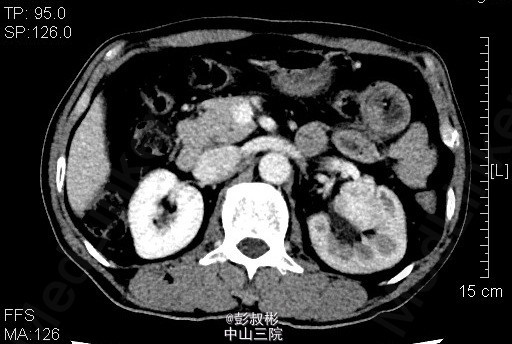

男性,51岁,发现左肾肿物2年余。反复左腰部隐痛2月余,无肉眼血尿。泌尿系B超:左肾中极见一个类圆形低回声光团,大小:30×26mm,边界不清,内部回声欠均匀。左肾实性占位病变。腹部CT:左肾占位病变,考虑为肾癌可能性大。